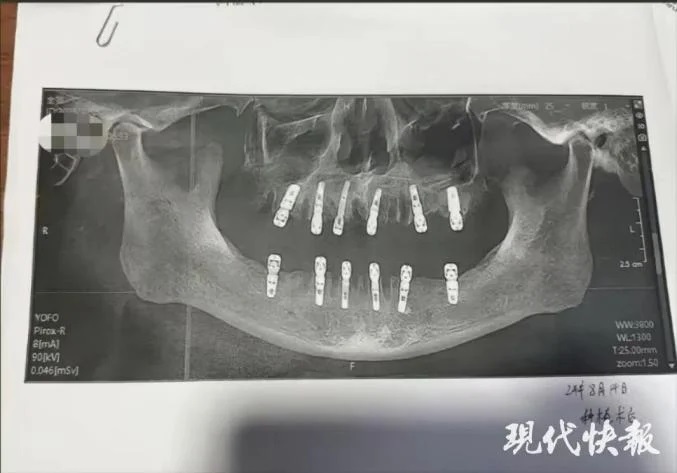

وأخبرت شو السلطات أن والدها عانى من آلام مبرحة طوال الأيام الثلاثة عشر الأخيرة من حياته، قبل أن يعاني من نوبة قلبية قاتلة في 28 أغسطس. والآن تريد المرأة تقديم المسؤولين إلى العدالة. ووفقًا لنموذج موافقة المريض، فقد حصل والد شو بالفعل على خلع 23 من أسنانه الطبيعية قبل حفر 12 ثقبًا في جمجمته وفكه لزراعة أسنان جديدة. تم إجراء كل هذا في يوم واحد، مما يعني أنه كان عليه أن يتحمل آلامًا لا يمكن تصورها بعد زوال تأثير التخدير. وعلى الرغم من أن عدد عمليات الخلع يبدو مفرطًا بعض الشيء لجلسة واحدة، إلا أن المتحدث باسم العيادة التي أجريت فيها العملية قال إن عدد الأسنان التي يمكن إزالتها في المرة الواحدة يجب أن يحدده الطبيب في استشارة وجهاً لوجه بناءً على الحالة الجسدية للمريض.

ووفقًا لسجلات مستشفى ديوي للأسنان، فقد تم إجراء عمليات الخلع الـ 23 بواسطة طبيب يُدعى يوان، وتشمل تخصصاته علاج قناة الجذر وإزالة ضروس العقل المدفونة وأطقم الأسنان الكاملة. وعلى الرغم من عدم وجود لائحة محددة حاليًا بشأن عدد الأسنان التي يجب خلعها في جلسة واحدة، إلا أن العيادة والطبيب يجب أن يأخذا في الاعتبار قدرة المريض على تحمل الألم وخطر الإصابة بالعدوى. وقال شيانغ غولين، مدير مركز طب الفم بمستشفى ووهان الرابع، لصحيفة "ذا بيبر": "كلما زاد عدد الأسنان التي يتم خلعها، زادت استجابة المريض للألم وزادت احتمالية الإصابة بعد العملية الجراحية".